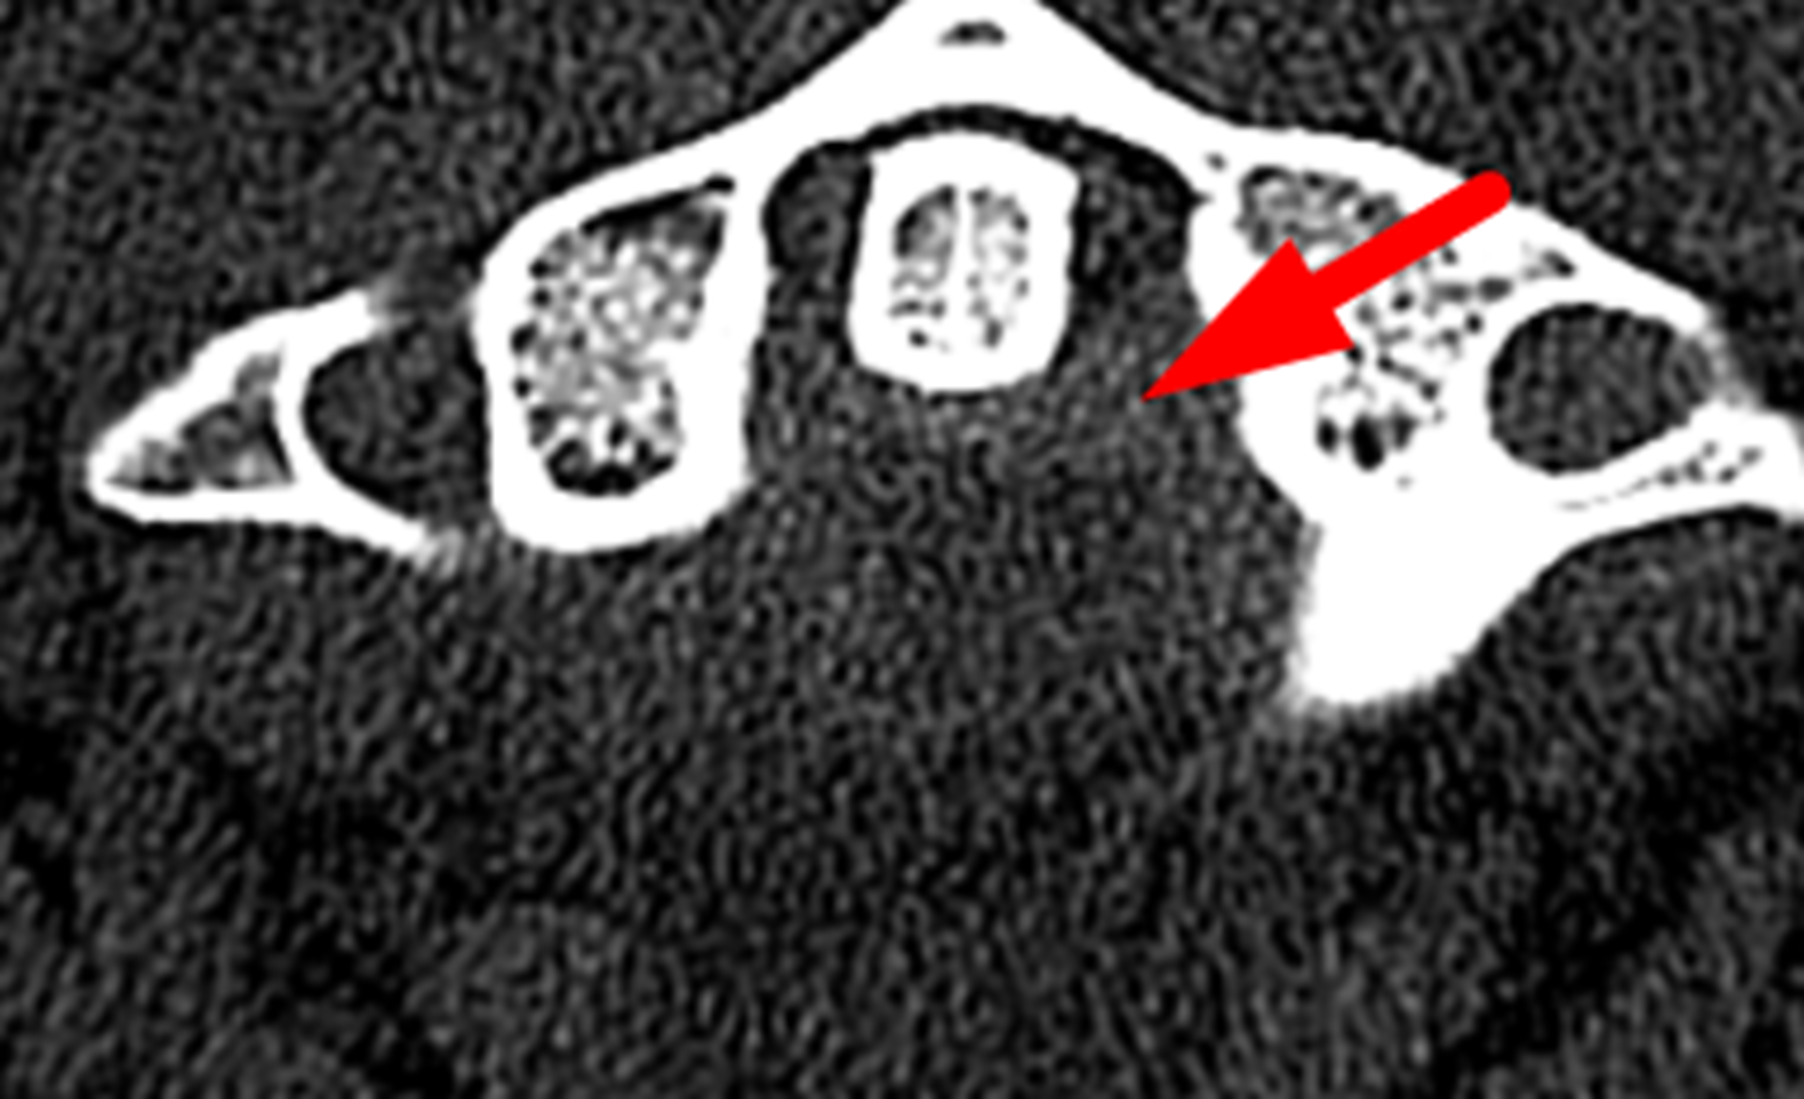

Red arrow: extra-axial hemorrhage posterior to the odontoid process.